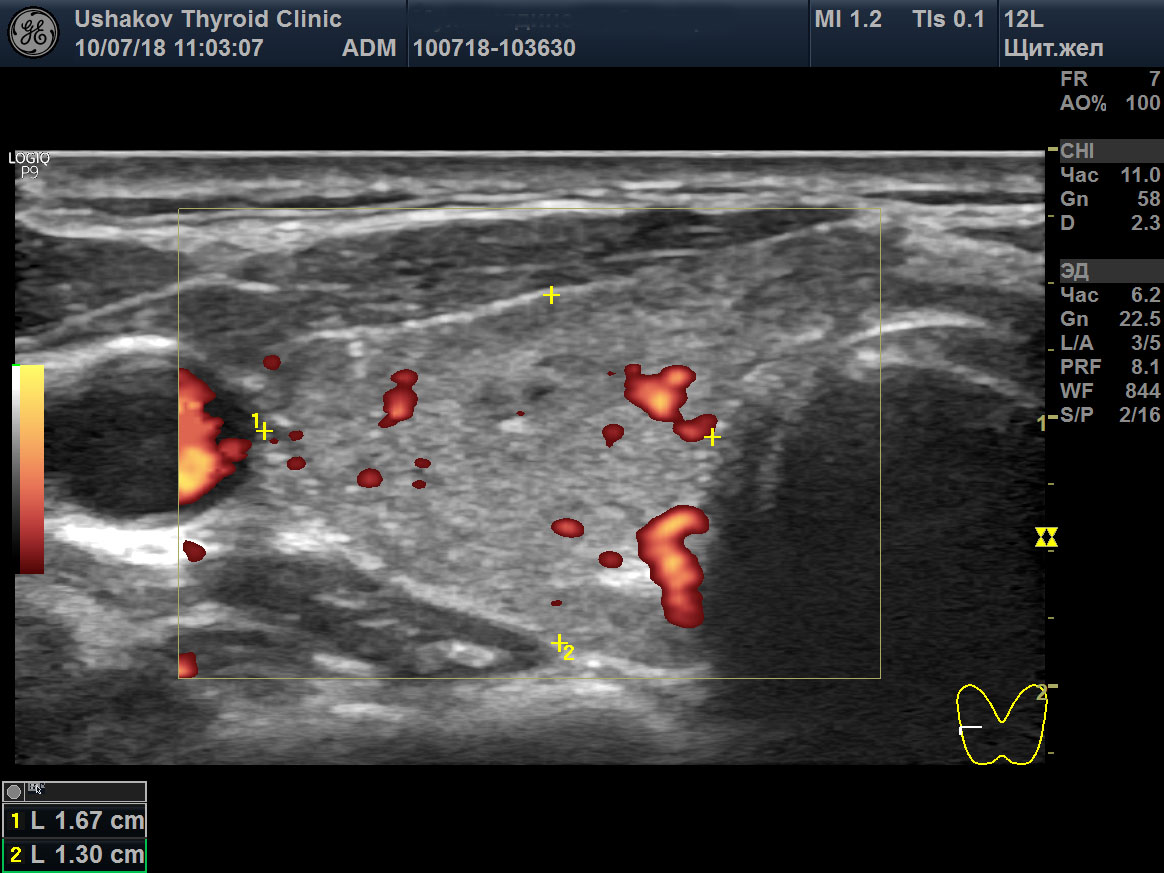

Цдк в узи щитовидной

Цдк в узи щитовидной 110 фото